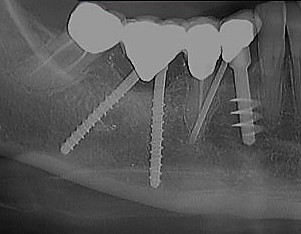

Una delle critiche che si fa all’implantologia italiana riguarda l’utilizzo di bipodi e tripodi e delle forche che si creano. L’implantologia di scuola italiana realizza questo genere di unità implantari da sempre e lo fa proprio perché l’esperienza clinica di centinaia di migliaia di casi spalmati su centinaia di operatori ha permesso di appurare che le forche sotto elementi implantari non sono assimilabili a quelle sotto elementi naturali, come appare ovvio, dato che le forche sotto unità implantari non possono determinare patologie parodontali per la mancanza di un elemento fondamentale: il tessuto parodontale. Il caso riportato è emblematico, rappresentando le condizioni peggiori in cui una forca implantare si possa trovare: sospesa nell’alveolo chirurgico fresco in caso di impianti postestrattivi.

Nella prima foto si vedono gli impianti inseriti contestualmente alla rimozione di un impianto sepolto colpito da grave perimplantite, nella seconda il controllo a sette anni di distanza che dimostra non solo che non c’è stata perdita ossea perimplantare, ma addirittura un fenomeno osteoriparativo che non solo ha riempito il difetto osseo lasciato dal precedente impianto sepolto rimosso, ma addirittura lo ha superato dimostrando un lieve accrescimento verticale